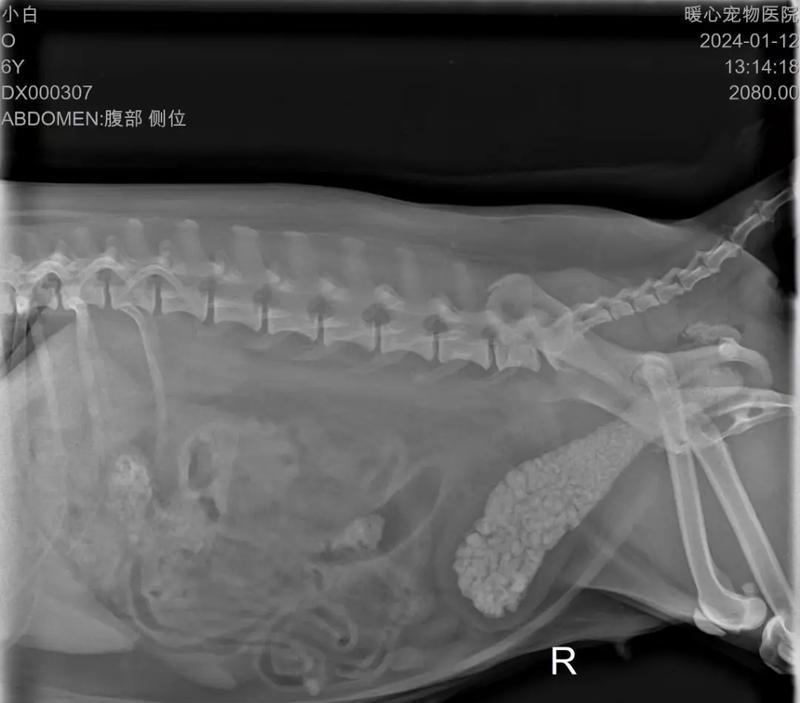

狗狗结石是一种常见的健康问题,它会给狗狗带来不适和疼痛。了解结石的症状是及时治疗和预防的关键。本文将介绍15种与狗狗结石相关的症状,并提供预防措施,帮助你更好地保护你的爱宠。

7.腹部触感异常:当你摸摸你的狗狗的腹部时,如果感觉到固体物质,可能是结石的存在。

15.急性腹痛发作:在结石阻塞尿道或导致感染时,狗狗可能会突然出现剧烈的腹痛。